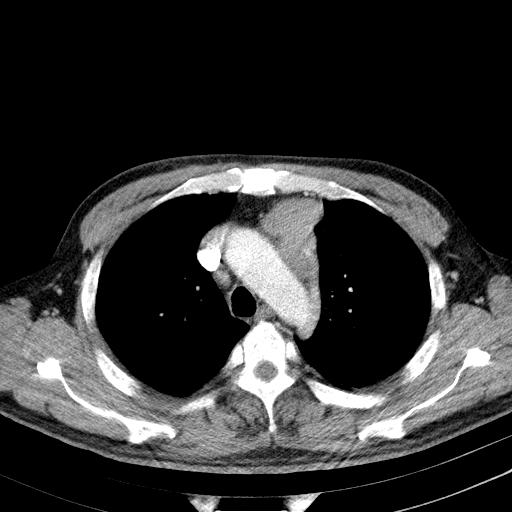

经典?纵膈多发肿大淋巴结。腹膜后未见异常。

还见胃窦壁增厚!转移亦有可能!

1)考虑淋巴瘤。2)双侧少量胸腔积液。

多发肿大淋巴结影,肝内改变需结合强化观察